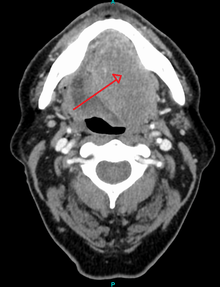

Head and neck cancer

_squamous_cell_carcinoma_histopathology.jpg)

Ninety percent[14] of cases of head and neck cancer (cancer of the mouth, nasal cavity, nasopharynx, throat and associated structures) are due to squamous cell carcinoma.